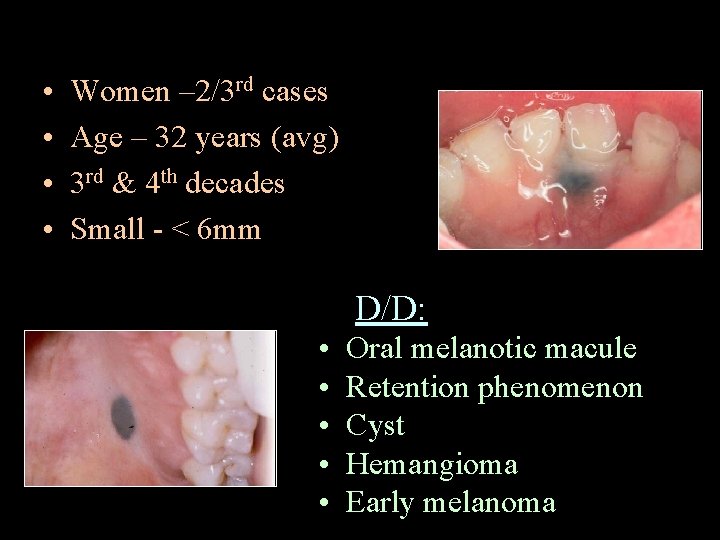

• • Women – 2/3 rd cases Age – 32 years (avg) 3 rd & 4 th decades Small - < 6 mm D/D: • • • Oral melanotic macule Retention phenomenon Cyst Hemangioma Early melanoma